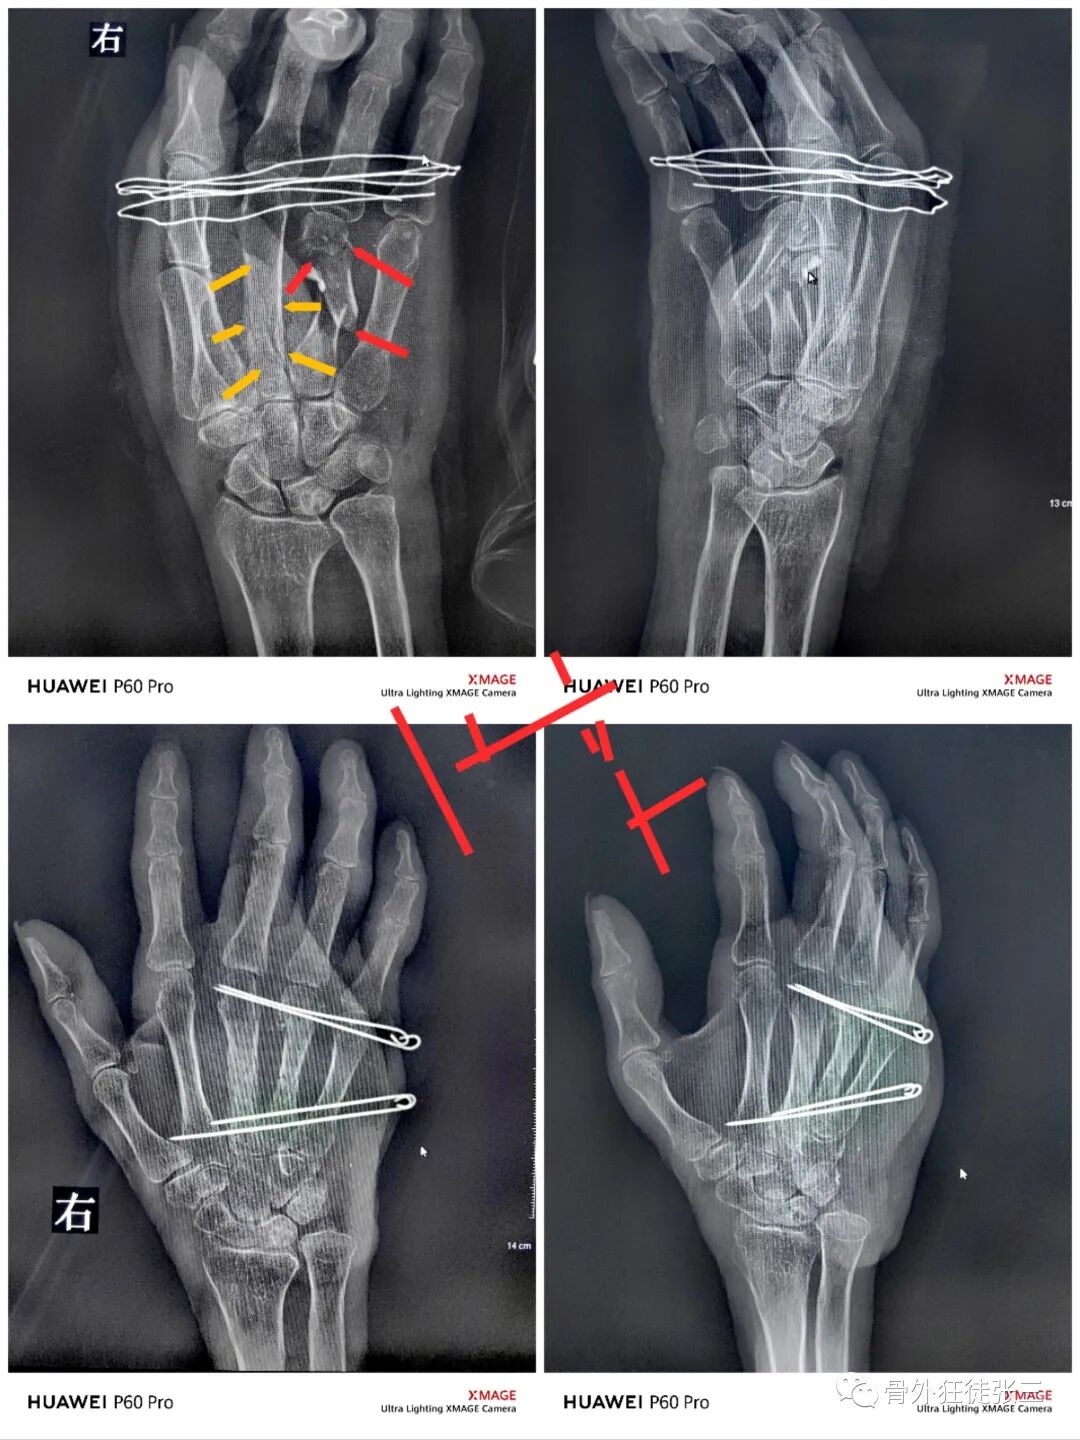

病例1,第5掌骨基底骨折,闭合复位克氏针支架,无需石膏,门诊手术,术后即刻恢复正常工作。

病例2,第4掌骨螺旋型骨折,经皮撬拔,克氏针支架。

病例5,开放性第3、4掌骨骨折,隔山打牛,克氏针支架。

病例6,开放性第2345掌骨骨折,克氏针支架

病例7,开放性掌骨,指骨骨折,克氏针内固定